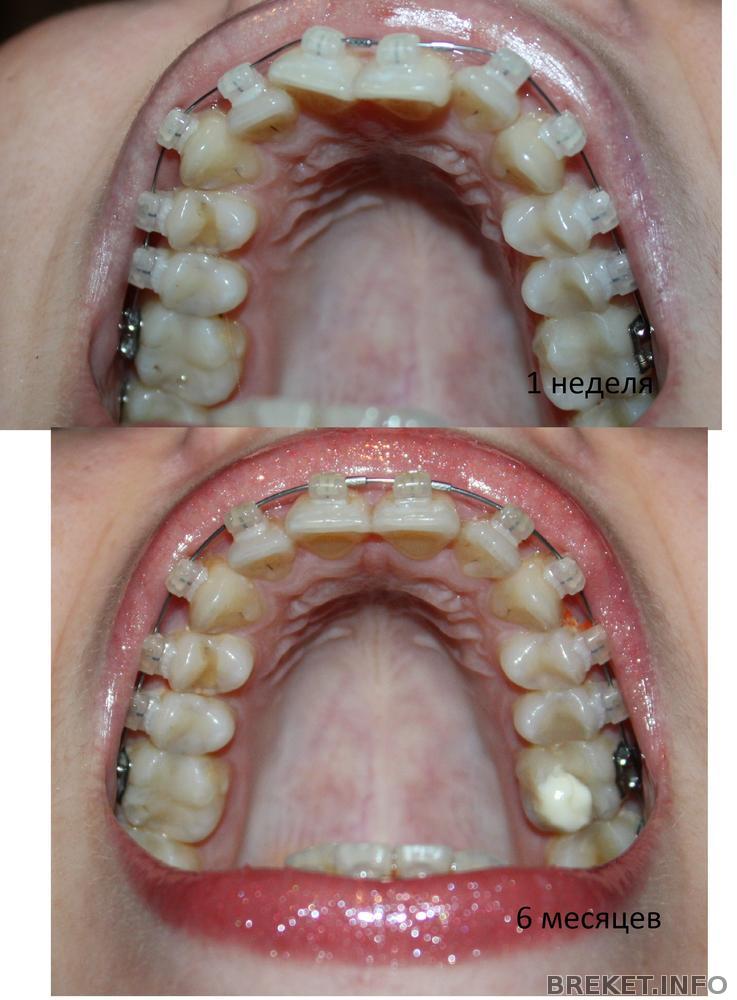

Всем привет! Пост будет коротким.... Неделя жуткая...((( От усталости, мне показалось, что моим зубкам 6 месяцев, сделала фотки, сравнила, немного расстроилась, что результат не такой хороший как мне хотелось бы....., Но все же он есть!!!, Из нового.., вчера мне поставили квадратную дугу на ВЧ и Пружину на НЧ , что бы делать место для одного зуба...., ЖУТКО БОЛИТ ВСЯ ЧЕЛЮСТЬ..., Никогда не болели так зубы с момента постановки БС..., но сейчас, это что то невыносимое, я не могу их смыкать..., а про покушать вообще молчу...((( голодаю одним словом...(( Прямоугольная дуга это жесть конечно...., но от нее жду хороших результатов!!!!

Прилагаю коллажи..., На которых как мне казалось, 6 месяцев, но посмотрев здесь, поняла что ошиблась на месяц...)) На фото нам 5 месяцев)))

Очень красивые зубки, челюсти стали кругленькие

и форма зубов тоже симпотная.